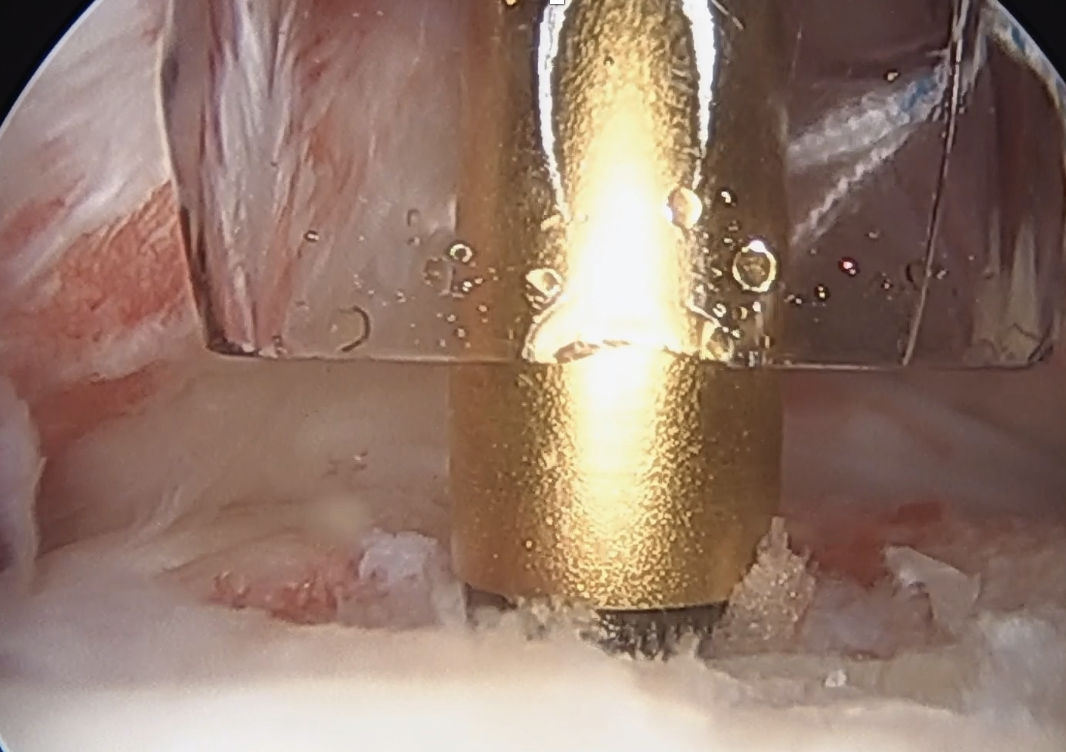

- debride footprint on lesser tuberosity

- insert anchor through anterior portal

Insert anchor through anterior portal into subscapularis footprint